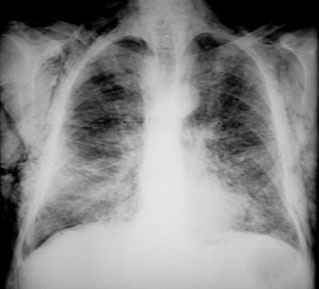

Note air in the soft tissues.